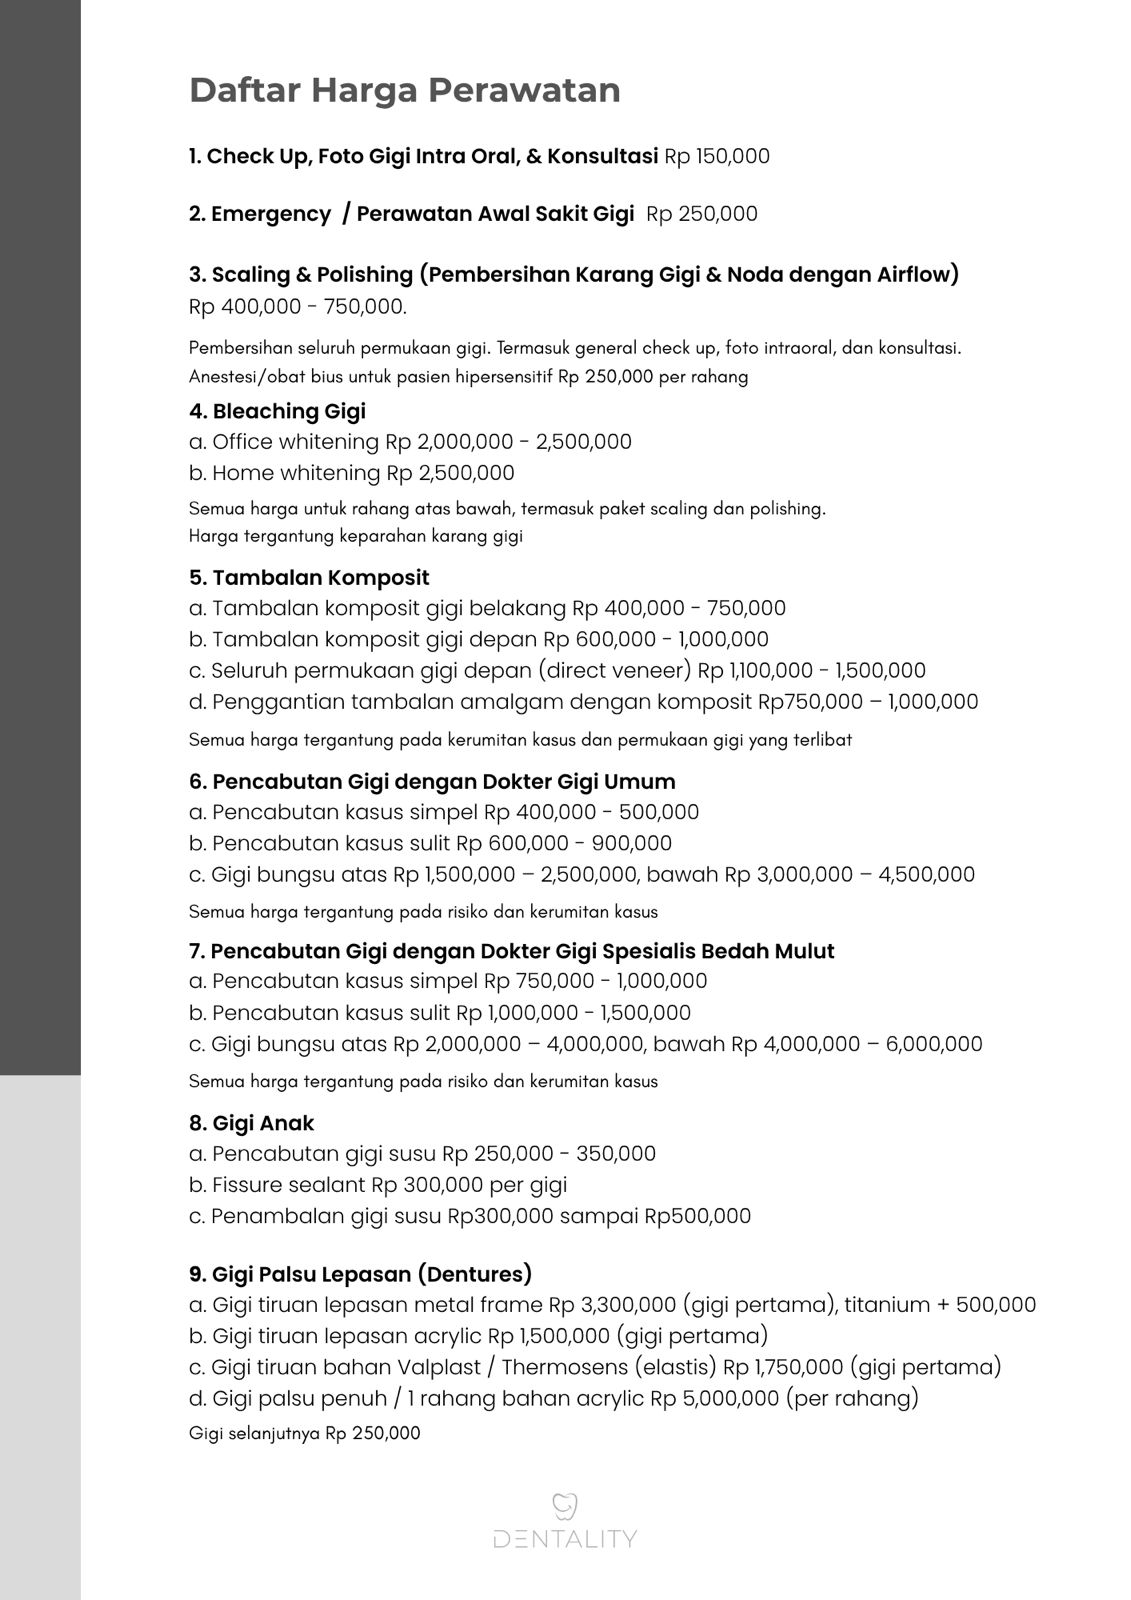

Semuanya, dari scaling, whitening, tambal gigi, hingga implant dan crown gigi.